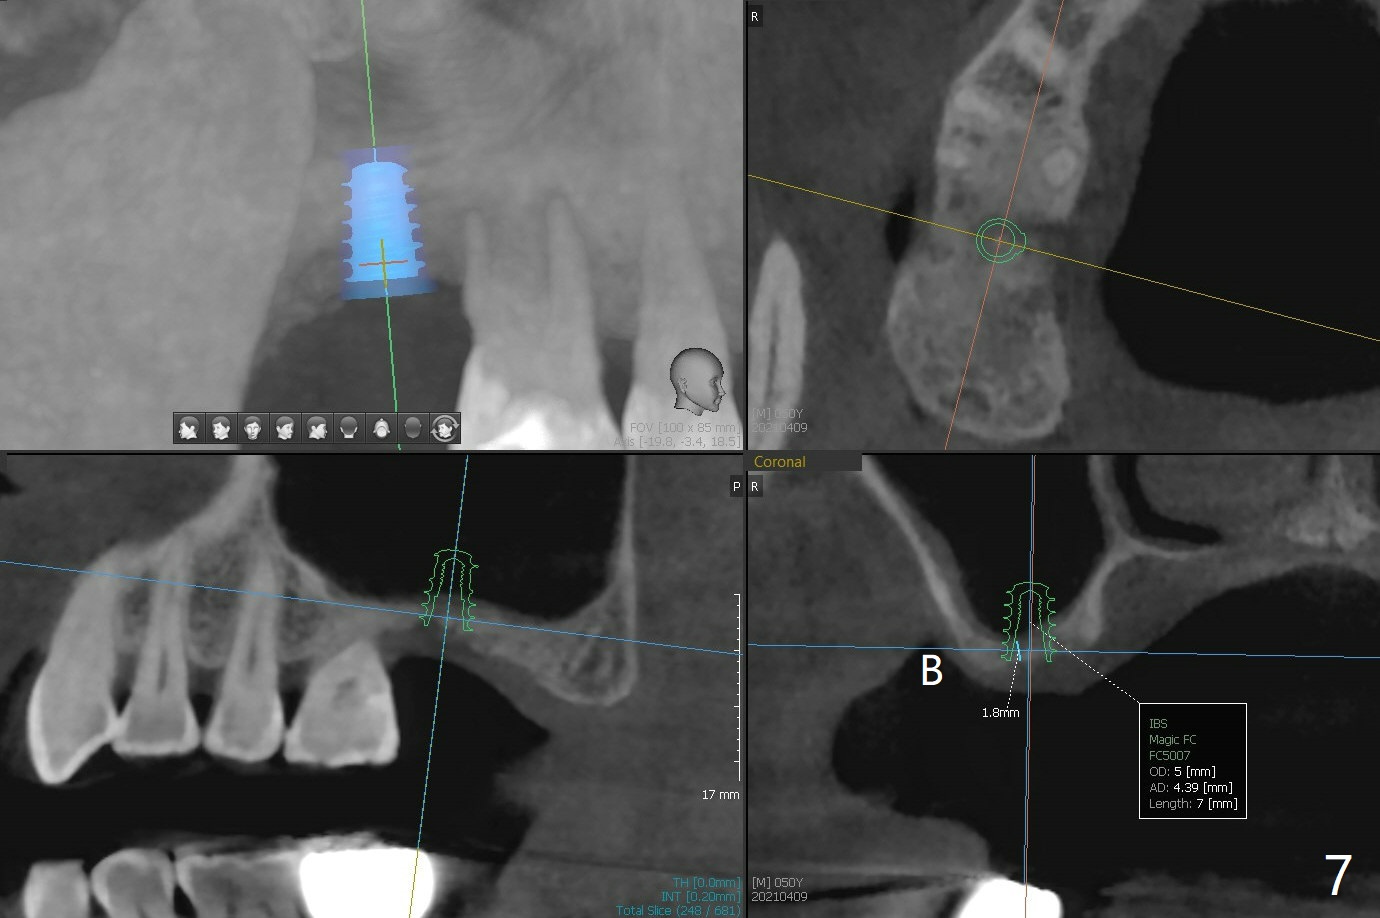

50岁男,二型糖尿病,对常用糖尿病药物无效,使用胰岛素也必须提高剂量,总之控制不好。总共种植四个,两个延期没问题,但是两个即刻均失败,似乎容易发炎,包括右上7(图一:* (螺纹暴露)),颊侧牙龈退缩(图二),牙冠取出后显示植体和基台偏腭侧(图三:P),其实植体没有整合,不费劲旋出植体,清除肉芽组织后,植入粘性骨粉(图四:*),覆盖PRF膜,GEM Cap,应用牙周胶水固定,然后间隙维持器,牙周敷料固位。右上7和左上7植牙取出后4个月和一年5个月骨质高度很低(图五)。右上7大约1.8毫米(图六)。准备植入5x7毫米植体(图七)。使用1毫米stopper钻头,然后Magic Lifter和PRF。术前口服Z Pack,术后Medrol Dose Pack。